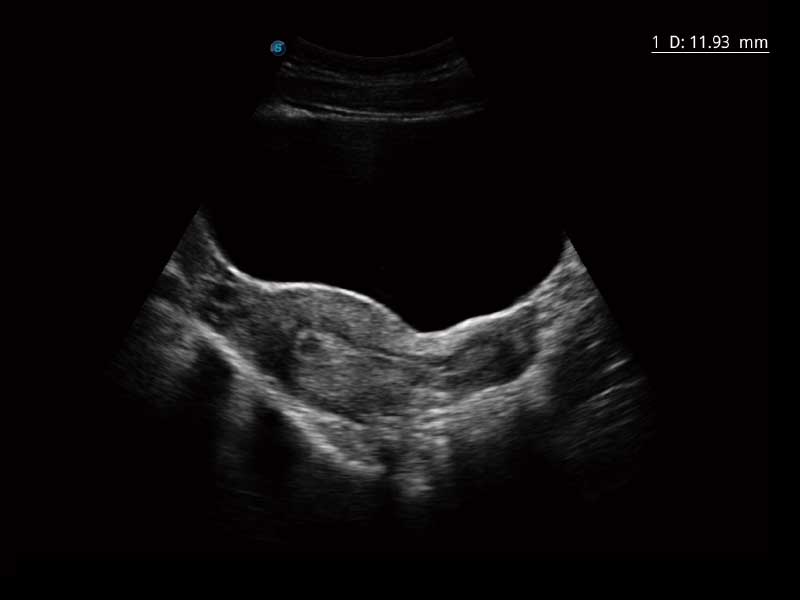

E2便携式彩色多普勒超声诊断系统采用专业的超声技术平台、高度集成化的硬件模块和结构设计、简便的操作流程、多探头接口设计,兼顾了优质图像、轻便机身以及台便两用的临床使用需求。

μ-Scan微米成像、空间复合成像、高分辨率血流成像。

高清液晶显示器、轻便机身、快速开/待机响应、专用台车。

单键操作,可快速优化多个二维及多普勒图像参数,获得优异图像效果。